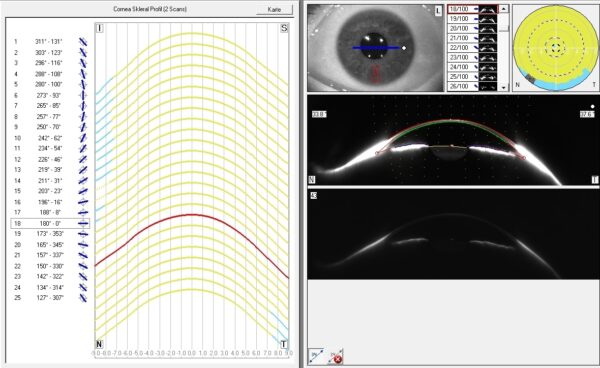

Mit der Pentacam AXL Wave wird dann Ihr Auge mit 138.000 Messpunkten exakt vermessen. Daraus entsteht ein präzises 3D-Modell von Sklera und Limbus, auf dessen Basis Ihre persönliche Freiform-Sklerallinse gefertigt wird – ein echtes Unikat, perfekt an Ihre Augengeometrie angepasst.

In einer Studie wurde gezeigt, dass die Form der Augen stark asymmetrisch ist. Nur 6% der Augen weisen eine primär peripher sphärische Form auf. Alle anderen Augen sind auf der Sklera asymmetrisch. Dies verdeutlicht die Notwendigkeit, auf die individuelle Augen-Form bei der Kontaktlinsenanpassung besser einzugehen.

Quadrantenspezifische Skleral-Kontaklinsen

Vier verschiedene Radien in vier Achslagen. Diese Linsen haben vier verschiedene periphere Abflachungs– und Tiefenwerte. Aufgrund des Anfertigungsprozesses, liegen diese unterschiedlichen Radien immer 45°Grad zueinander.

Freiform Skleral-Kontaktlinsen

Diese Linsen haben je nach Ausführung 8-72 verschiedene periphere Abflachungs– und Tiefenwerte. Aufgrund des Anfertigungsprozesses, liegen diese unterschiedlichen Radien in einem Abstand von 5°Grad zueinander.